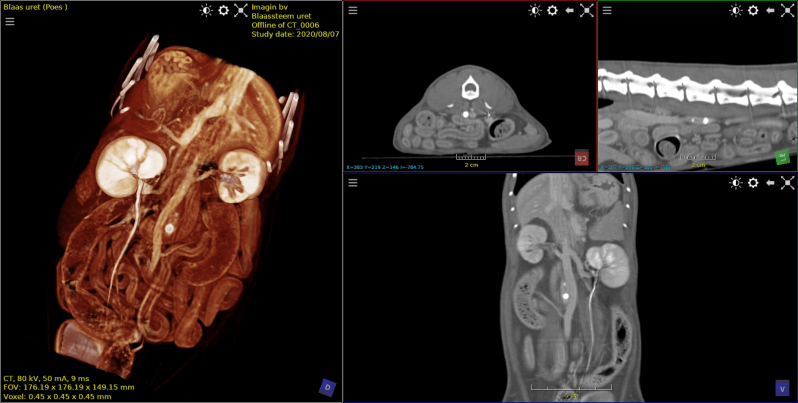

Deze kat had een voorgeschiedenis van FLUTD.

Het diertje werd aangeboden met strangurie.

Op de röntgenfoto zijn geen afwijkingen zichtbaar.

Op de Ct-beelden echter is het gruis zichtbaar in de blaas.